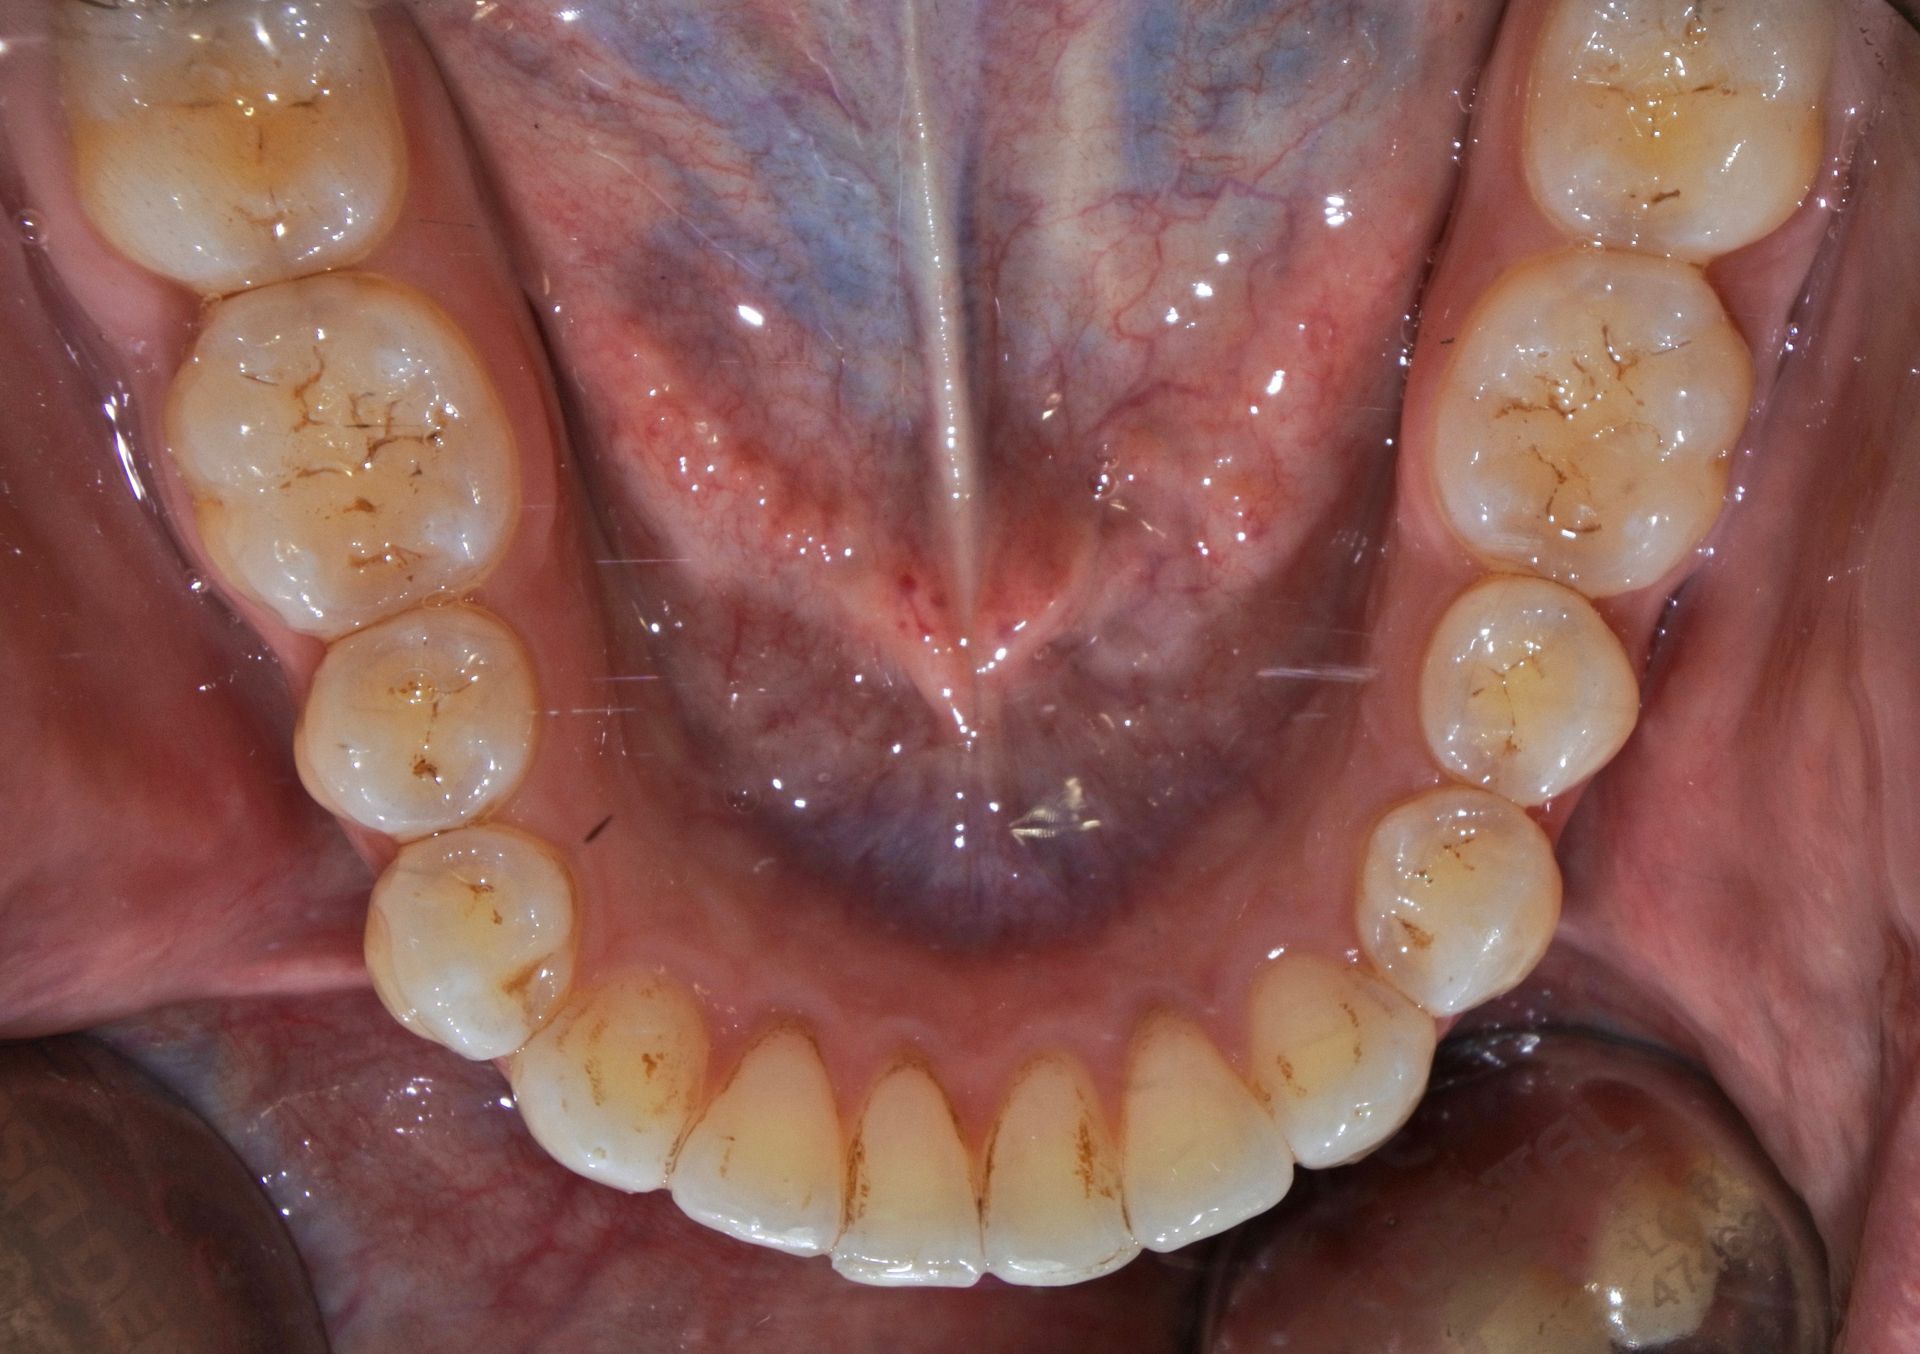

Utilizzando lo scanner iTero Element, lo specialista effettuerà una scansione 3D delle arcate ed attraverso un software dedicato definirà un piano di trattamento specifico per ciascun paziente.

Tale software rende possibile previsualizzare il risultato finale del trattamento grazie ad una simulazione digitale.